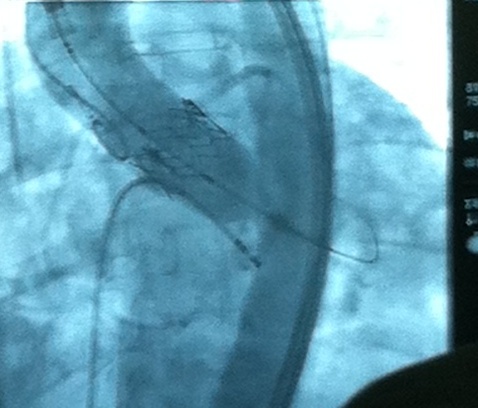

Под контролем рентгена клапан ввели в сердце, затем аорту, зафиксировали, а затем окончательно разместили вместо старого больного клапана. На фотографии – рентгеновское изображение имплантированного клапана, заключенного в хромовый стент.